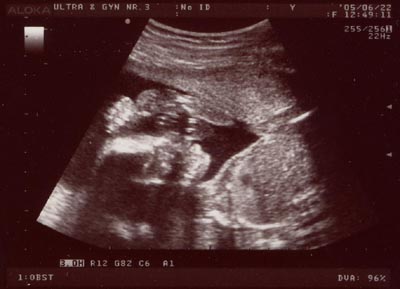

Ultraljud

v 19

Nu fick vi reda på den riktiga åldern och mina föräldrar blev återigen förvånade när de fick veta att jag var nog ytterligare 1,5 vecka äldre än de tidigare trott, så det här är istället i v 21! Jag är alltså 18 veckor på nedanstående bilder och redan ganska snygg, eller hur? Framför allt vig - ni som sett sådana här bilder förut ser nog att jag har både händer och fötter uppe vid huvudet...